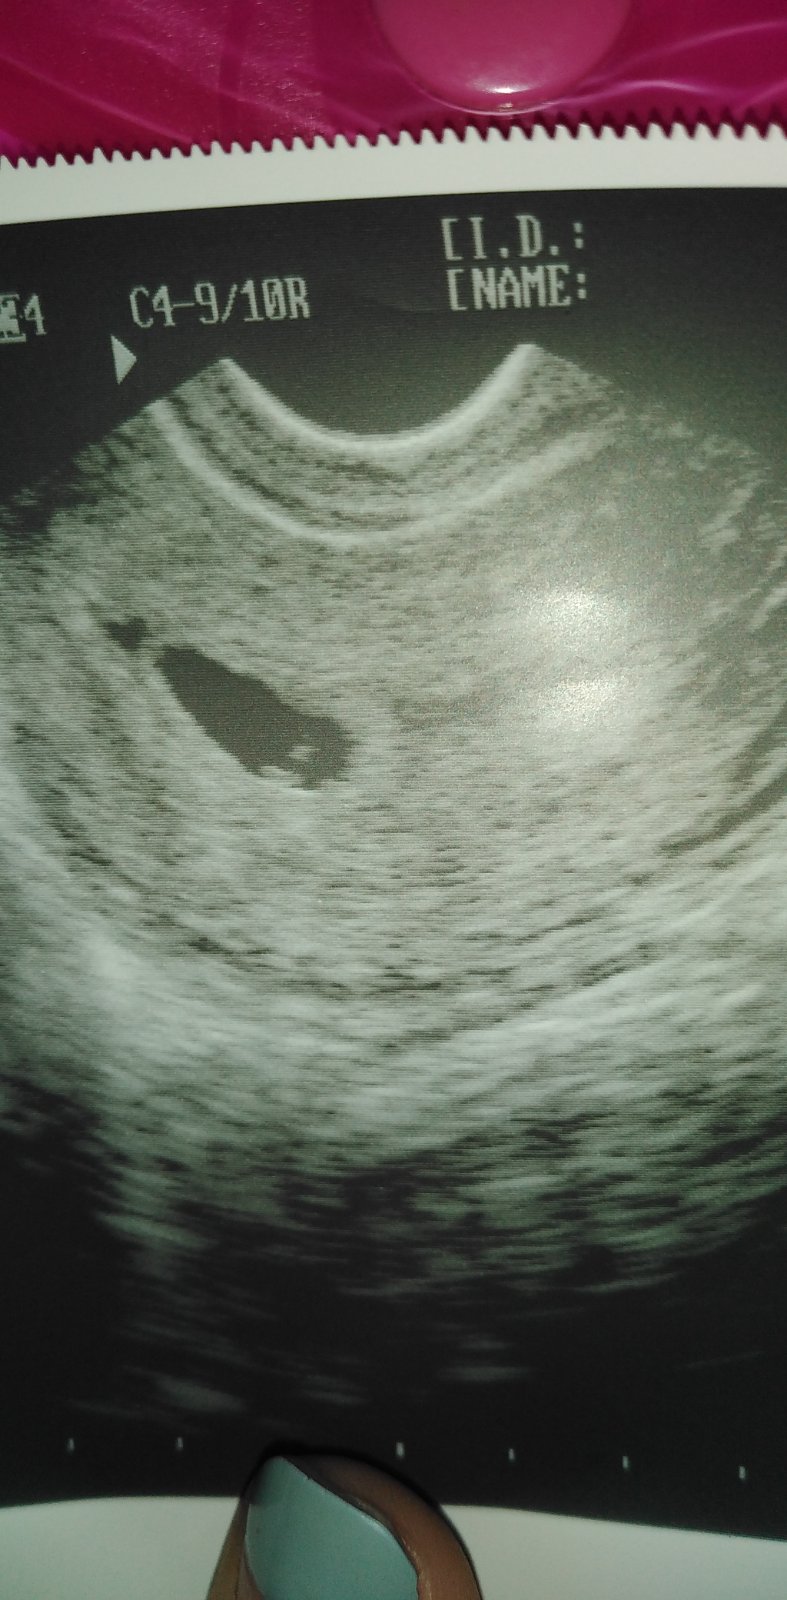

@andreasvo sice nic moc moje doktorka má starý ultrazvuk 🤣

@rebekabebe to je nádhera 😘 takový krásný ultrazvuk jak tam jde krásně vidět ❤️ Cítíš břicho ? Je každé těhotenství stejné ? Prosím vem v potaz i ty co nevyšli